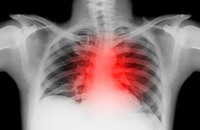

2016年2月,欧洲心脏病学会(ESC)下属的急性心血管治疗协会(ACCA),发布了关于急性心力衰竭(AHF)患者从急诊科安全出院的建议书,同步在线发表于《European Heart Journal: Acute Cardiovascular Care》。ESC建议,只有在明确诱因、确定危险分层和评估治疗效果之后,AHF患者才可以从急诊科安全出院。

5月21日,《European Heart Journal》刊发了由欧洲心脏学会(ESC)心力衰竭委员会、欧洲急诊治疗学会和流行病学急诊治疗学会联合制定的《急性心力衰竭院前和院内管理指南》。该指南实用性强,特摘取指南的要点进编译如下。

心力衰竭患者由于存在心脏重塑和神经-体液活化,可导致心律失常的发生率增加或者心律失常病情加重。2015年8月,欧洲心律学会(EHR)/欧洲心力衰竭协会(HFA)联合发布了心力衰竭合并心律失常的共识文件,并得到了美国心律学会(HRS)及亚太心律学会(APHRS)的支持。

2014中国心衰指南公布:五大亮点体现新理念与新思维

2013ACCF/AHA心力衰竭指南解读